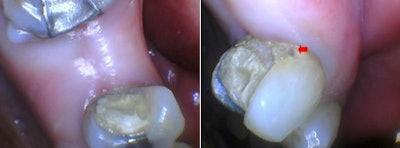

Tooth #5 had endodontic treatment and needs a core and full-coverage restoration. Tooth #3 will be treated conservatively with a composite restoration if the patient does not choose a fixed partial denture. Figures 2 and 3 show the patient's preoperative condition.

For the progression of this case in the photos, a red arrow is used in the distobuccal of tooth #5 to denote a reference point relative to tissue level.